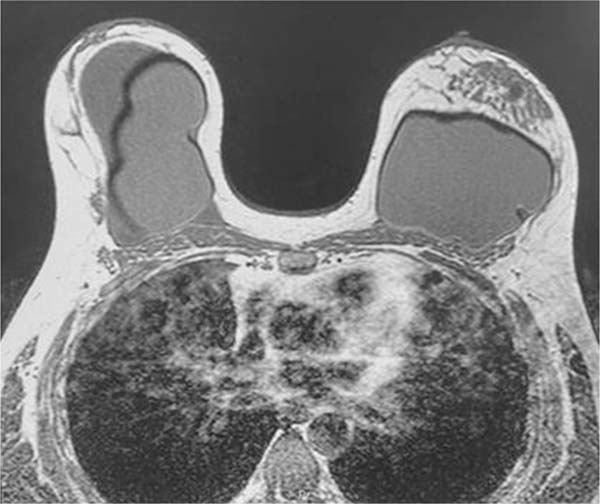

Na ressonância magnética, apresentava volumosa coleção intracapsular na mama direita, com conteúdo heterogêneo, associado a realce e espessamento do invólucro e da cápsula fibrosa, compatível com processo inflamatório e contratura capsular, não podendo desconsiderar a possibilidade de BIA-ALCL. O Sistema de Relatórios e Dados de Imagiologia Mamária (Breast Imaging-Reporting and Data System [BIRADS], em inglês) foi classificado como 4 (►Fig. 2).